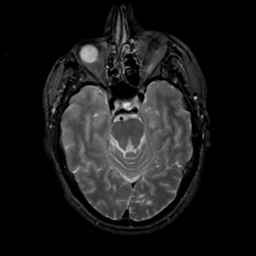

MR Study #15, June 9, 1991 -- Slice #17

[Home][Help][Clinical][Tour 1][Tour 2] Slice 17